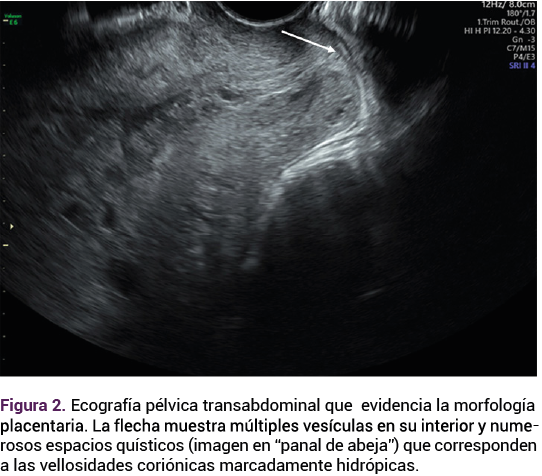

El reporte anatomopatológico y microscópico identificó mola hidatiforme parcial coexistente con un feto (Figuras 3, 4 y 5). Durante el seguimiento, la paciente no tuvo complicaciones aparentes y mostró un descenso significativo en las concentraciones de la gonadotropina coriónica humana.

<strong>Figura 3</strong>

Figura 3.